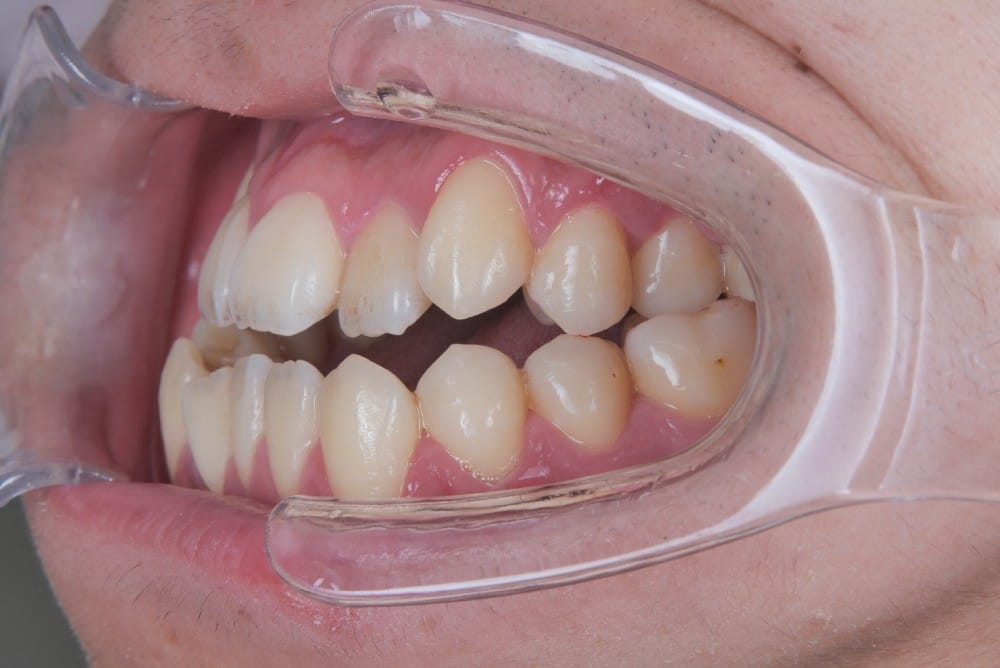

この子は、中学生の女の子で、受け口、横顔が気になるとのことでご来院されました。

治療前の様子

分析をしますと

- 骨格的な上下あごの前後差は中等度

- 噛み合わせの位置も下あごの奥歯が半分くらい前にズレていた

- 上の前歯が前に傾斜、下の前歯が内側に傾斜しているにもかかわらず、受け口

というケースで、外科的な処置も検討するようなケースでした。

患者さまに外科的な手術の選択肢も提示しましたが、希望されず、横顔の変化はおそらく起こらないことを納得の上、治療をスタートいたしました。

このような奥歯の移動量が大きい症例では、マウスピースだけでは難しいことがあり、カリエールとよばれる装置を補助的に使用し、上下の噛み合わせの前後関係を整えることで、手術を行わずに機能面と見た目の両方が改善することがあります。

一時的に前歯は噛み合わせが開いていますが、受け口の矯正では、最終段階で前歯ばっかりあたって奥歯がしっかり噛まないということも起こりやすいので、あえて狙って動かしています。

ここから上下透明なマウスピースに変え、仕上げていきました。

治療後の写真

矯正治療によって前歯の被さりを改善することで、口元の突出感が減り、横顔がやわらかい印象に変化しました。